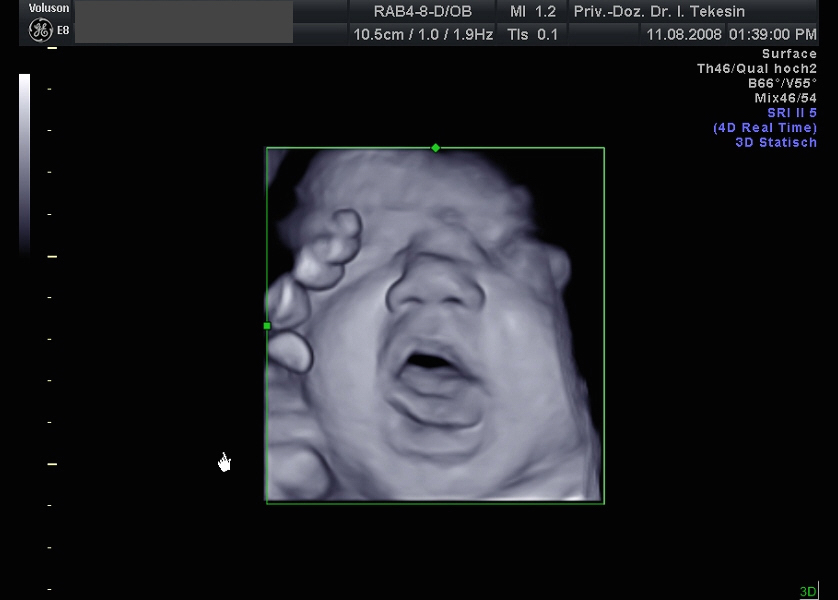

3D-/4D-Ultraschall (optional)

Immer mehr werdende Eltern interessieren sich für die faszinierenden Bilder, die dieses Verfahren liefert. Die plastische, dreidimensionale Darstellung der Oberfläche des Gesichts und anderer Körperregionen wird durch spezielle Bildrekonstruktion in schnellen Rechnern erreicht. Auch einzelne innere Organe oder „Gefäßbäume“ können von allen Seiten betrachtet werden. Viele dünne Schnittebenen (2D) werden zu einer gemeinsamen 3D-Sichtweise im Computer des Ultraschallgerätes zusammengeführt. Unter einem 4D-Ultraschall versteht man darüber hinaus eine 3D-Ultraschalluntersuchung unter Echtzeitbedingungen. Anstatt nur statische Bilder anzuzeigen, erfasst ein 4D-Ultraschall die Bewegungen des Kindes, weshalb er auch als „Live-3D-Ultraschall“ bezeichnet wird.

Diese Vorgehensweise ermöglicht äußerst realistische Bilder, bei denen sogar Gestik und Mimik des Kindes in bewegten Sequenzen festgehalten werden können. Die Untersuchung kann wie auch der normale Ultraschall während des gesamten Schwangerschaftszeitraums durchgeführt werden. Möchte man das Ungeborene komplett sehen, wird die 12. bis 16. Schwangerschaftswoche empfohlen, die Zeit zwischen der 28. und 33. Schwangerschaftswoche eignet sich besonders zur präzisen Darstellung einzelner Körperteile

Ein gähnendes Kind in der 38. Woche

Ein freches Kind in der 38. Woche (3D-Darstellung)